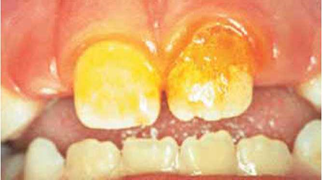

En la actualidad las medidas preventivas anticaries que agregadas al cepillado dental, consideradas como las más eficientes, son el uso de fluoruros y la estimulación del calcio en la saliva, a esto se agrega el xylitol y el Recaldent® en las gomas de mascar. Éstos son agentes preventivos científicamente comprobados que proporcionan mayor reducción en el índice de lesiones cariosas9),(10(Figura 3).